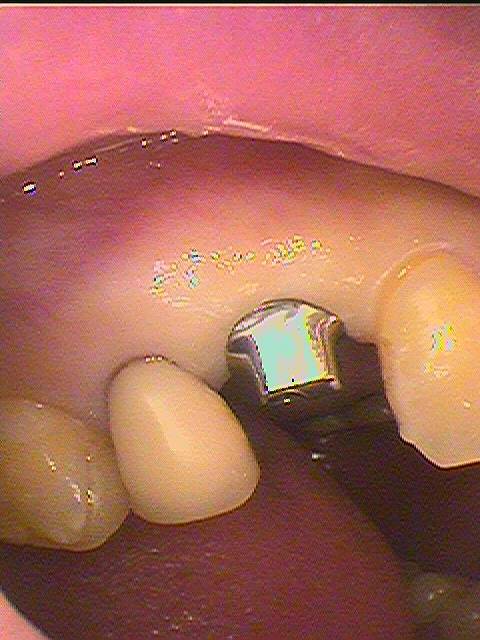

左上4番のインプラントの上部構造の様子になります

カスタムアバットメントを作成しています

カスタムのアバットメントを作成し、歯肉形態、マージン設定をしていきます

マージン設定は歯肉縁上としています

オールセラミックにて作成しています